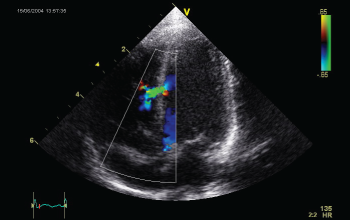

La Ecocardiografía es un examen diagnóstico que enfocado a la obstetricia y ginecología permite conocer el estado en que se encuentran el embrión-feto durante el proceso de gestación y el estado de la mujer previo y posterior al embarazo. Con ayuda del Diplomado en Ecografía Obstétrica y Ginecológica el participante aprenderá cómo hacer una valoración de los genitales internos de la mujer para identificar cualquier patología que pudiera presentar, así como también ayudara a monitorear el proceso de gestación del embrión-feto. El Diplomado Internacional de Ecografía Obstétrica y Ginecológica se encuentra Acreditado por la Sociedad Mundial de Medicina para la Educación Médica Continua y Certificado por 40 puntos de valor curricular por la World Federation for University Education, además se encuentra avalado por la STPS (Sistema de Registro de la Capacitación Empresarial SIC110307957-0013).